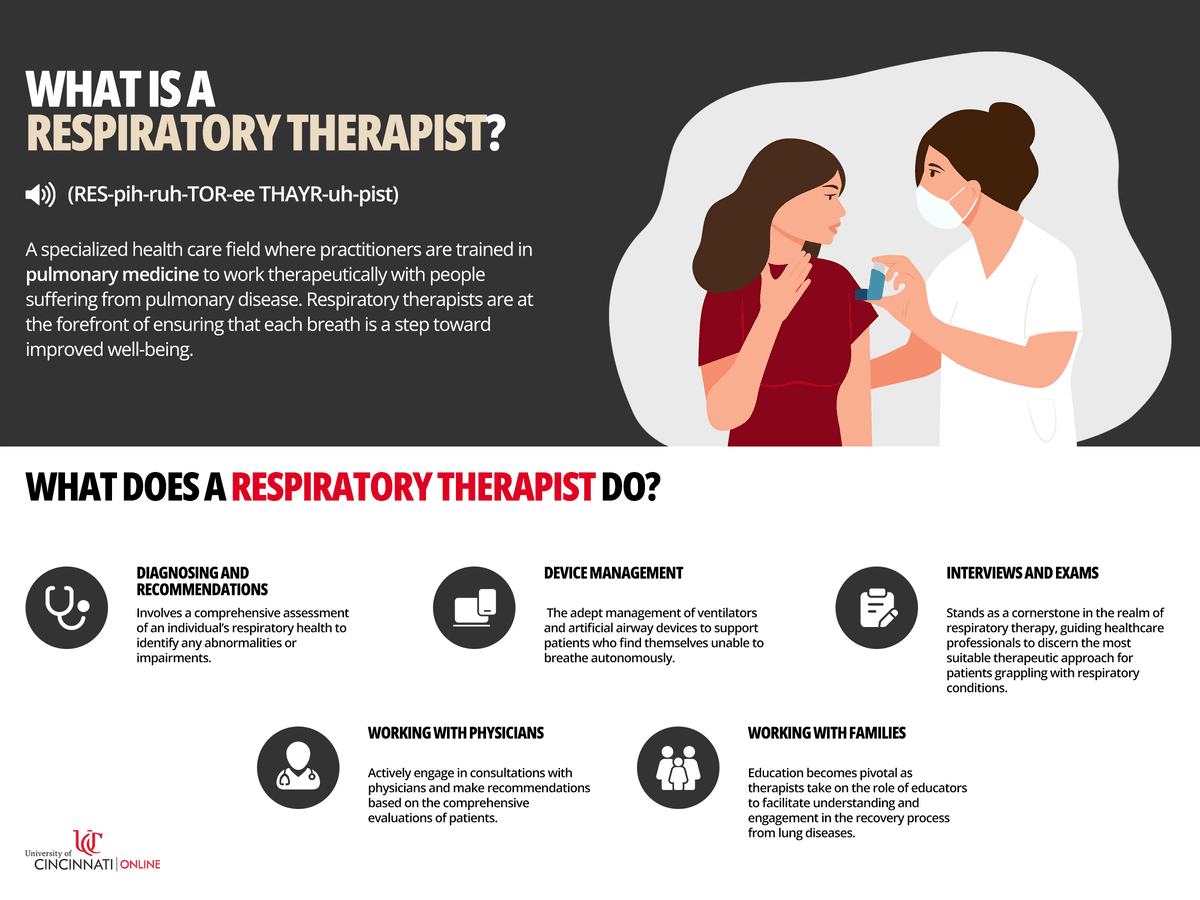

What Does a Respiratory Therapist Do?

As unsung heroes of healthcare, it is important that we highlight that respiratory therapists play a crucial role in the lives of patients facing respiratory challenges. In this blog, we will celebrate them by focusing on their daily responsibilities, shedding light on the expertise and dedication required to navigate the complexities of lung health. From diagnosing respiratory disorders to implementing personalized treatment plans, respiratory therapists are at the forefront of ensuring that each breath is a step toward improved well-being. Join us as we delve into the daily routines, compassionate care, and the evolving landscape of respiratory therapy, showcasing the invaluable contributions these professionals make to the healthcare ecosystem. To all the prospective students who are looking to further their education and complete their bachelor’s degree, this our salute to you as professionals and our thanks for playing a vital role the healthcare ecosystem.

- Respiratory therapists (RTs) diagnose, treat, and manage breathing and lung disorders—providing life-saving care through expertise in ventilators, diagnostic tests, and patient education.

- Working closely with physicians, patients, and families, RTs create personalized treatment plans and empower individuals to take charge of their respiratory health.

- From critical care units to outpatient clinics, respiratory therapists adapt their expertise to a wide range of environments—ensuring patients receive specialized care tailored to their unique respiratory needs.

What Are the Main Job Responsibilities of a Respiratory Therapist?

#1 - Diagnosing and Recommendations

Diagnosing lung and breathing disorders involves a comprehensive assessment of an individual's respiratory health to identify any abnormalities or impairments. This process often includes a combination of:

#2 - Device Management

#3 - Interviews and Exams

#4 - Working with Physicians

Collaboration lies at the heart of effective respiratory care. Respiratory therapists actively engage in consultations with physicians and make recommendations based on the comprehensive evaluations of patients. By synthesizing information gathered from interviews, physical exams, and diagnostic tests, respiratory therapists are able to contribute

#5 - Working with Families

Empowering patients and their families through education becomes pivotal as therapists take on the role of educators to facilitate understanding and engagement in the recovery process from lung diseases. By providing clear and accessible information about the nature of respiratory conditions, available treatment options, and lifestyle modifications, respiratory therapists enable patients and their families to make informed decisions regarding their healthcare journey. This educational component extends beyond the immediate treatment phase, fostering a proactive approach to managing and preventing respiratory issues. Through effective communication and personalized guidance, therapists give patients the ability to take charge of their respiratory health. Ultimately, this emphasis on education serves as a catalyst for patients and their families to navigate the complexities of their condition and maximizes the potential for recovery and long-term well-being.

The work respiratory therapists do every day combines a blend of expertise, compassion, and unwavering dedication. From diagnosing respiratory disorders and managing ventilators to conducting patient interviews and offering crucial education, these healthcare professionals work tirelessly to enhance the respiratory well-being of individuals. When looking at their daily routines, it becomes evident that respiratory therapists are not merely practitioners of a profession; they are advocates for life, orchestrating a symphony of care that extends far beyond the confines of a hospital room or clinic. Their commitment to ensuring that every breath counts, coupled with their profound impact on patients and families, underscores the indispensable role they play in the intricate tapestry of healthcare. We celebrate the respiratory therapists whose daily efforts breathe life into the pursuit of a healthier, more vibrant future for all. Thank you again!